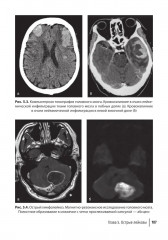

%text%